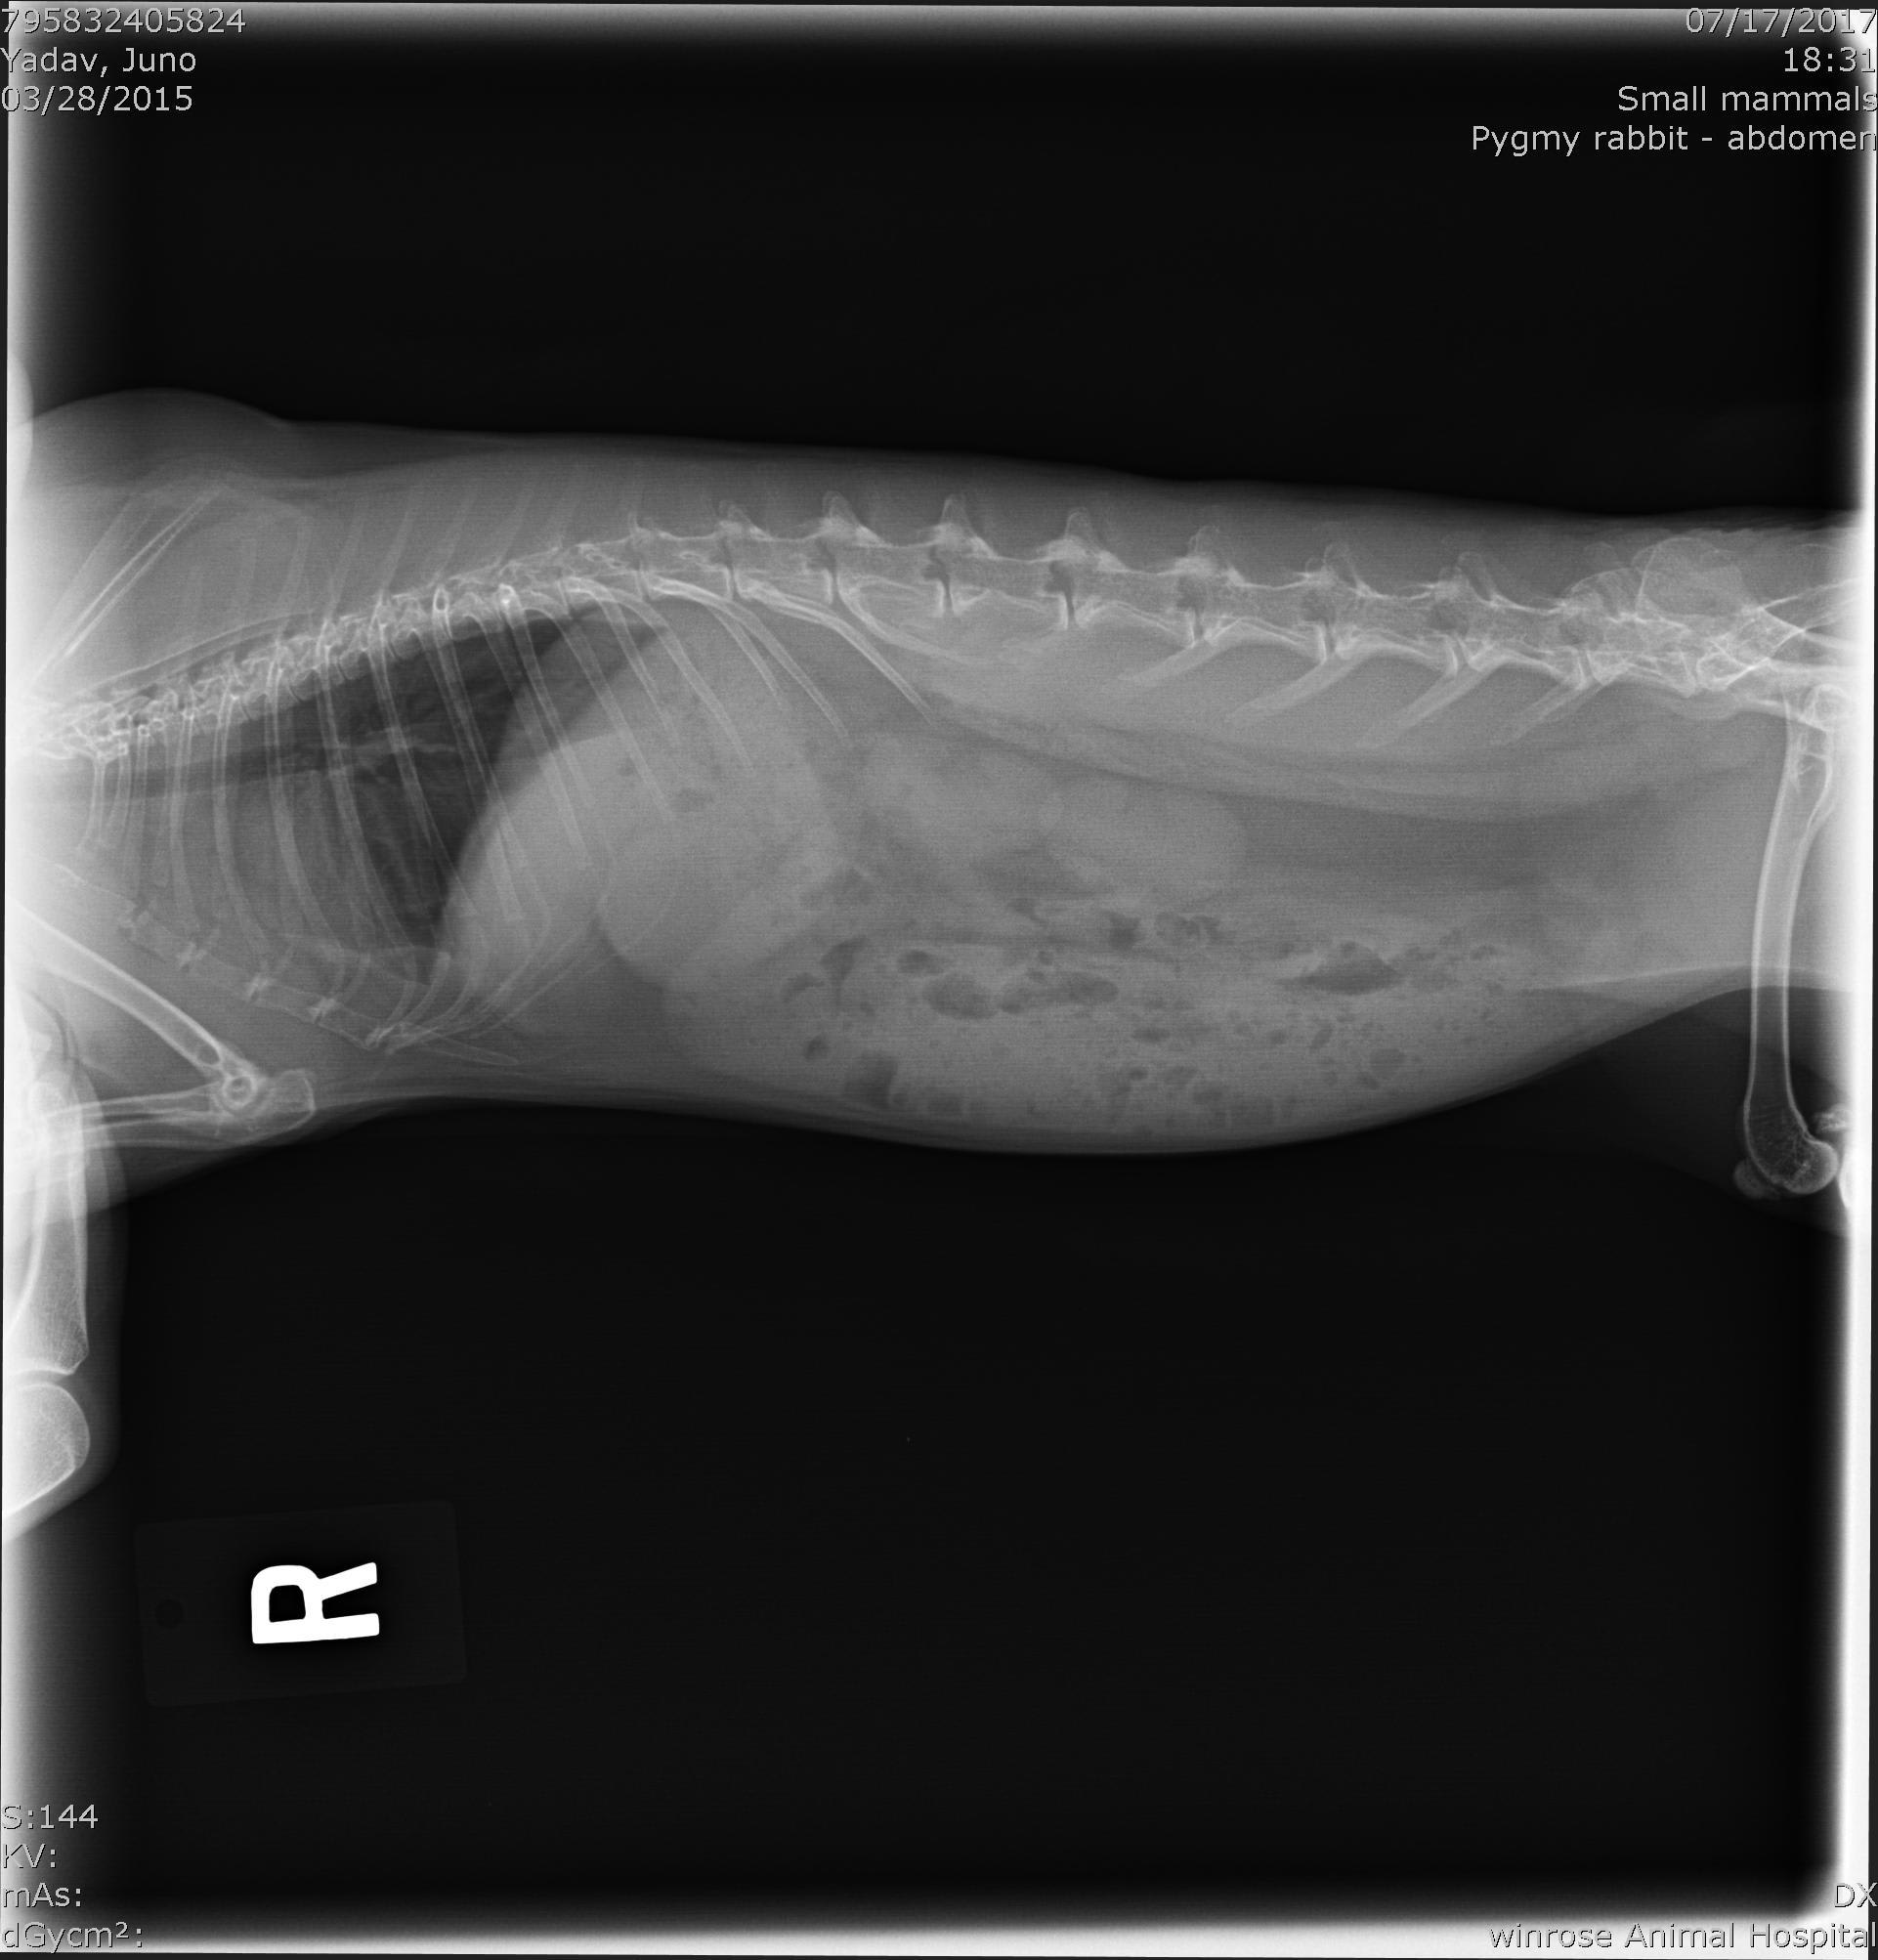

Hie there! I have a dutch dwarf bunny. Attached are his x-rays. Please can you take a look and advise me on pathological changes in them. History: Stopping pooping a week back, a vet noticed tenderness in his lower stomach area. He was put on Amoxicillin, cisapride and Eloxyn. After a week, pooping was still pretty small, weight loss of about 200 grams and food preference was only greens. I was feeding critical care but stopped because he was eating greens. This is the x-ray from day before.

There appears to be a lot of stool in the colon. I don't see any severe pathology though. I would recommend a few things: 1. STOP the Amoxcillin. I hate going against what another veterinarian has presbribed but Amoxicillin is not a good antibiotic for rabbits. It can be dangerous because of the likelihood of it negatively effect the GI Tract. I don't see any indication that an antibiotic is needed in your rabbit based on what you have stated in the history. 2. Continue the Cisapride and Eloxyn (if you still have some). The cisapride will help get the GI tract moving. He needs to stay on this drug until the motility of the GI tract is back to normal. 3. Keep feeding the Critical Care on top of the regular diet. Here is an article on GI stasis in rabbits that may help you. http://myhouserabbit.com/rabbit-health/gi-stasis-in-rabbits-a-deadly-condition/ They often take weeks to return to normal after being diagnosed with stasis. I hope this helps. Best wishes and I hope Juno gets back to normal soon!